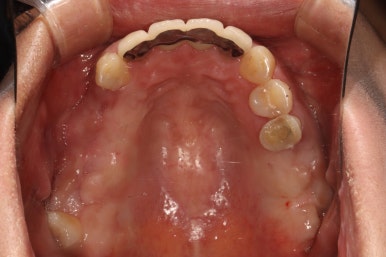

위턱 교합면입니다.

가장 드라마틱하게 바뀐 곳 중 하나인데요,

자기 자리를 잃어버렸던 치아들은 제거되고, 앞니는 지르코니아 크라운과 레진치료로 깨끗한 모습을 되찾았습니다.

썩었던 사랑니도 발치되었고 어금니 부위는 이제 깔끔한 스트라우만 임플란트 + 지르코니아 크라운 조합으로 마무리되었군요.